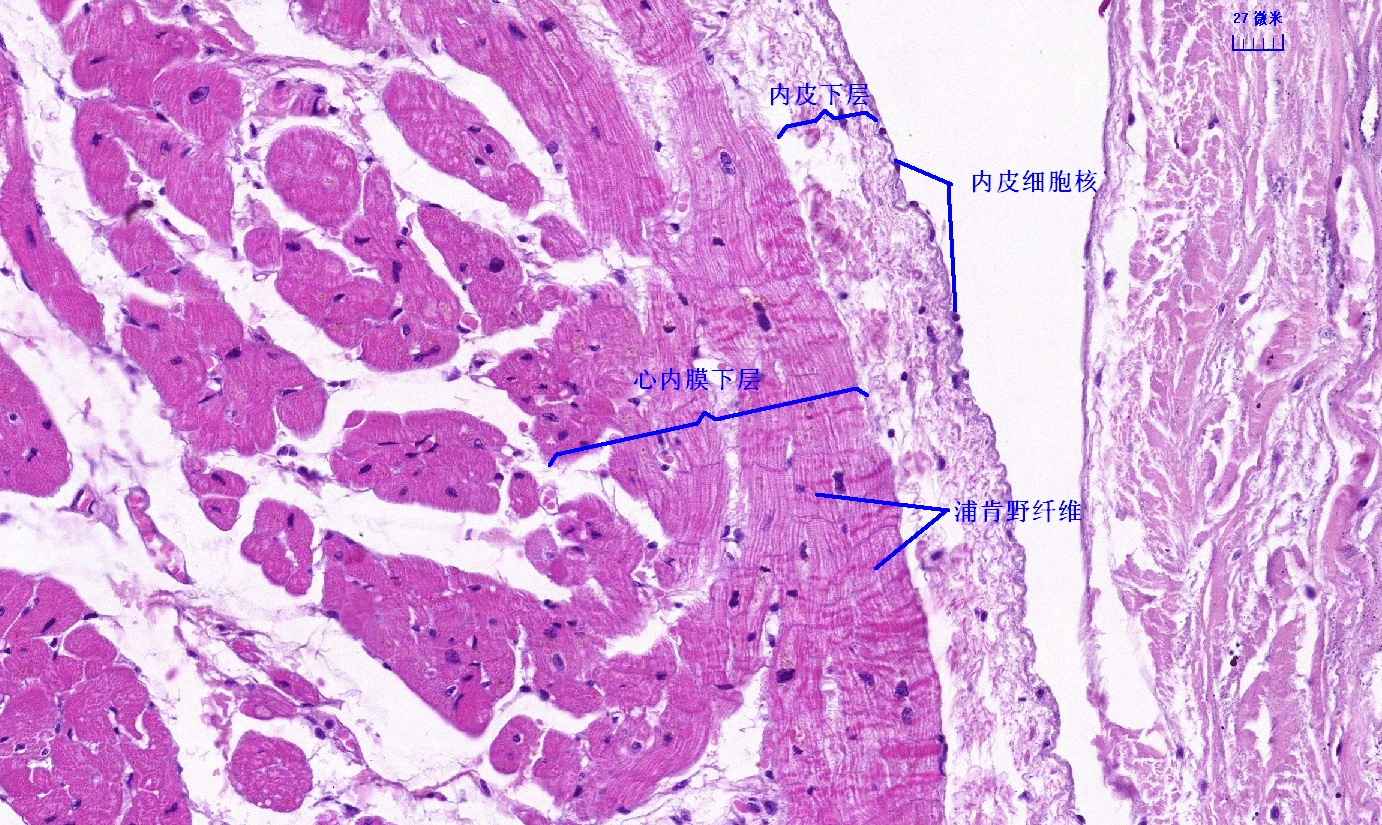

6 第六单元 循环系统

6.1 循环系统切片库

6.2 循环系统微课

6.3 循环系统课件